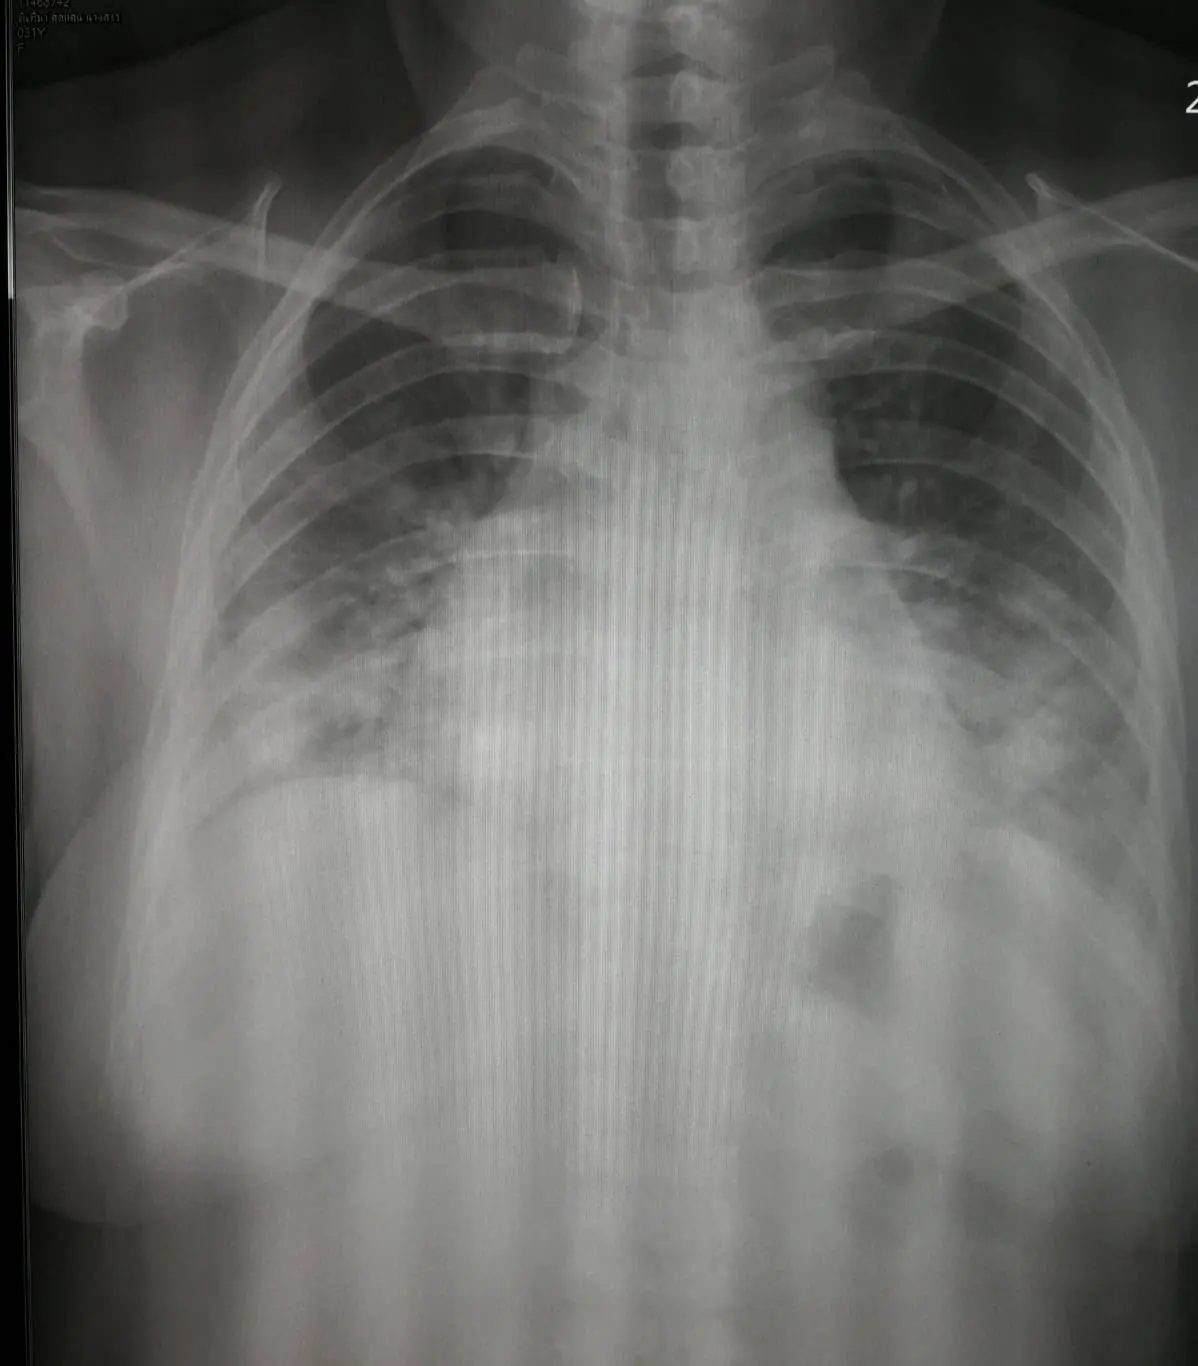

“ภาพเอกซเรย์ปอดที่คุ้นตาแพทย์กลับมาแล้ว ศึกพม่าตอนนี้รุกหนักจากชายแดนประเทศมาสู่ชายแดนตะวันตกของกรุงเทพแล้ว วันนี้มาปฏิบัติภาระกิจพิเศษในโรงพยาบาลเป้าหมายสองแห่ง ด้านหนึ่งในฐานะครูที่มาช่วยลูกศิษย์เตรียมการในโรงพยาบาลเพื่อรับมือผู้ป่วยโควิด อีกด้านหนึ่งในฐานะโรงพยาบาลแม่ข่ายปริมณฑลด้านตะวันตกของกรุงเทพ พบว่าศึกครั้งนี้คงระบาดวงกว้างได้ในสองสามวันนี้

เจ้าหน้าที่ที่เกี่ยวข้องกำลังทำงานกันอย่างหนักเพื่อควบคุมในชุมชน ที่น่าเป็นห่วงคือผู่ป่วยที่ต้องรับไว้ในโรงพยาบาลทั้งที่ไม่มีอาการไปจนถึงอาการรุนแรง หนึ่งใน 30+ รายเป็นดังรูปต้องใช้ออกซิเจนอัตราไหลสูง แต่ยังร่วมมือรักษาด้วยการนอนคว่ำให้มากเข้าไว้ อาการทั่วไปยังไม่น่าเป็นห่วง กังวลว่าอาจต้องเตรียมการล็อคดาวน์เฉพาะพื้นที่เสี่ยงหรือไม่